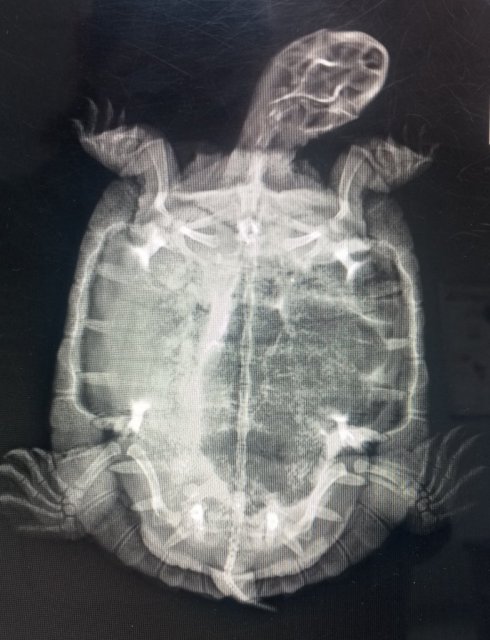

Консультанты moth Ваше имя: Мария Локация: Москва Опубликовано: 25 марта 2024 Консультанты Опубликовано: 25 марта 2024 @Марина Б здравствуйте! запишитесь на очный приём с черепахой https://cherepahi.ru/servisy/catalog/rossiya/spravochnik-krasnoyarskij-kraj-krasnoyarsk/ с такими симптомами нужно делать рентген и осматривать очно

Марина Б Ваше имя: Марина Локация: Красноярск Опубликовано: 26 марта 2024 Автор Опубликовано: 26 марта 2024 Съездили мы к ветеринару. Бронхопневмония у нас. Предлагали стационар. Я отказалась. Чересчур накладно. Будем сами лечиться. Вес 334 грамма. Съездили мы к ветеринару. Оцените наши назначения. Бронхопневмония у нас. Предлагали стационар. Я отказалась. Чересчур накладно. Будем сами лечиться. Вес 334 грамма.